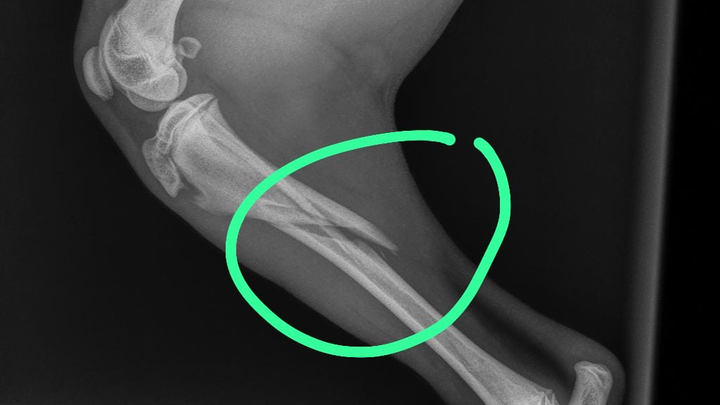

is percy ik zamel geld in voor me lieve kleine pup Bintang hele hoge kosten woord dit poot gebroken ik ken dit niet alleen zo op hoesten ik hoop dat mensen me kunnen helpen